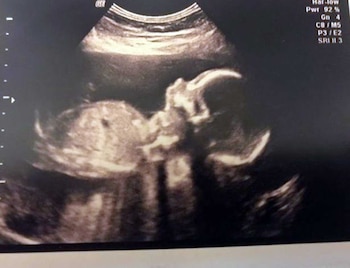

Ocurrió en marzo de 2014. Laura Gallazzi desarrollaba un embarazo de 25 semanas. Rompió bolsa. El líquido inundó sus piernas y salió de urgencia al hospital. Estaba aterrada. Sería muy difícil que sobreviviera a tal emergencia.

Corrió al Hospital Ninewells de Dundee, Reino Unido. Estaba mentalizada con que su pequeño hijo -para quien había elegido el nombre de Steven– sería prematuro y tendría dificultades. Todo tipo de pensamiento recorrió su cabeza en esos pocos minutos. Sin embargo, los médicos le indicaron que el bebé estaba bien y que lo mejor era que permaneciera un tiempo más en el vientre. Igualmente la mantuvieron bajo observación en el centro médico.